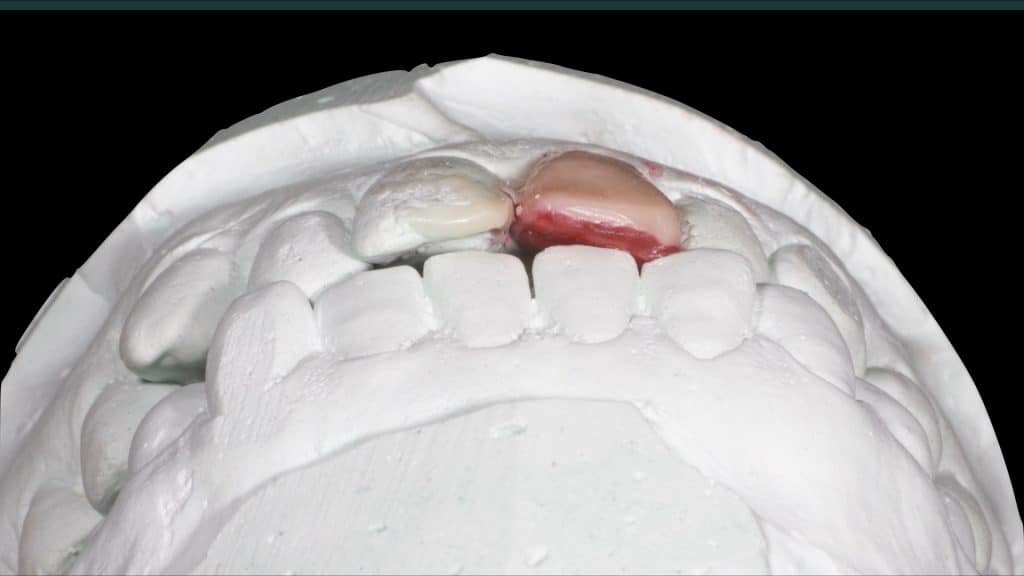

A 27-year female patient with dislodged Resin bonded FPD. She had that FPD for past few years, it had metal wings on palatal surfaces of UR1 and UL2 and a post like metal extension into the root canal of UL1. There was gingival abscess due to fractured root segment most probably due to extended metallic post like structure. Immediate implant placement (IIP) and Immediate restoration (IR) was planned for this patient.